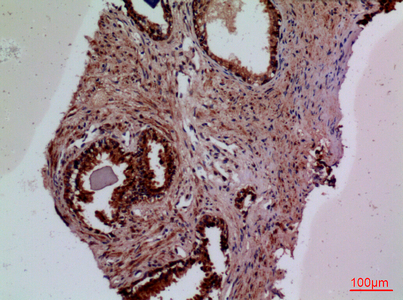

WB,IHC-P,IF-P,IF-F,ICC/IF,ELISA

WB 1:500-1:2000, IHC-P 1:100-300, ELISA 1:20000, IF-P/IF-F/ICC/IF 1:50-200

This gene encodes coagulation factor III which is a cell surface glycoprotein. This factor enables cells to initiate the blood coagulation cascades, and it functions as the high-affinity receptor for the coagulation factor VII. The resulting complex provides a catalytic event that is responsible for initiation of the coagulation protease cascades by specific limited proteolysis. Unlike the other cofactors of these protease cascades, which circulate as nonfunctional precursors, this factor is a potent initiator that is fully functional when expressed on cell surfaces. There are 3 distinct domains of this factor: extracellular, transmembrane, and cytoplasmic. This protein is the only one in the coagulation pathway for which a congenital deficiency has not been described. Alternate splicing results in multiple transcript variants.[provided by RefSeq, May 2010],function:Initiates blood coagulation by forming a complex with circulating factor VII or VIIa. The [TF:VIIa] complex activates factors IX or X by specific limited protolysis. TF plays a role in normal hemostasis by initiating the cell-surface assembly and propagation of the coagulation protease cascade.,induction:TF expression is highly dependent upon cell type. TF can also be induced by the inflammatory mediators interleukin 1 and TNF, as well as by endotoxin, to appear on monocytes and vascular endothelial cells as a component of cellular immune response.,online information:The Singapore human mutation and polymorphism database,online information:Tissue factor entry,similarity:Belongs to the tissue factor family.,